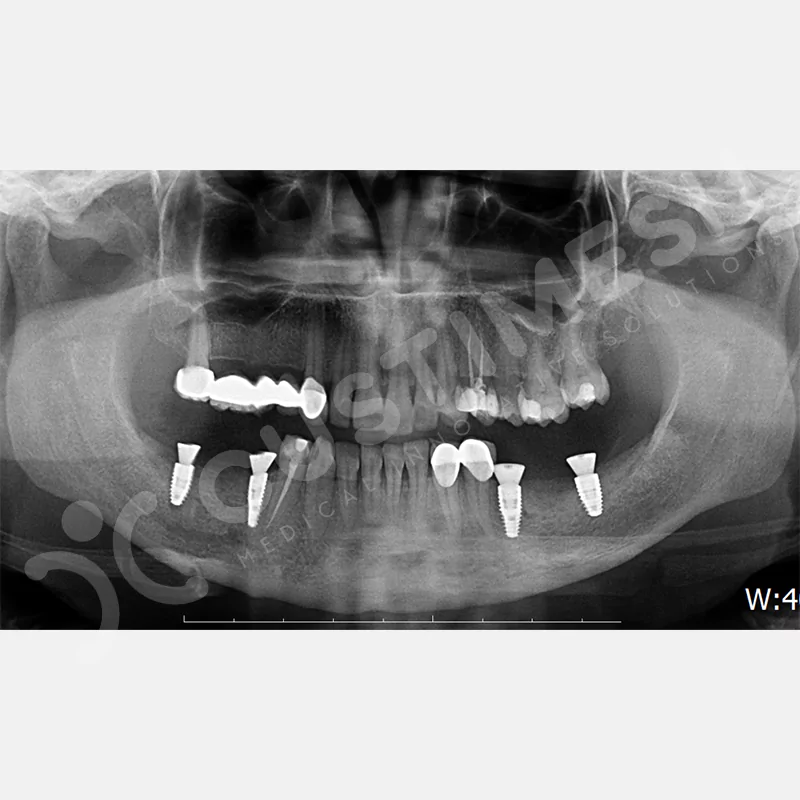

VAKA 1

VAKA 2

VAKA 3